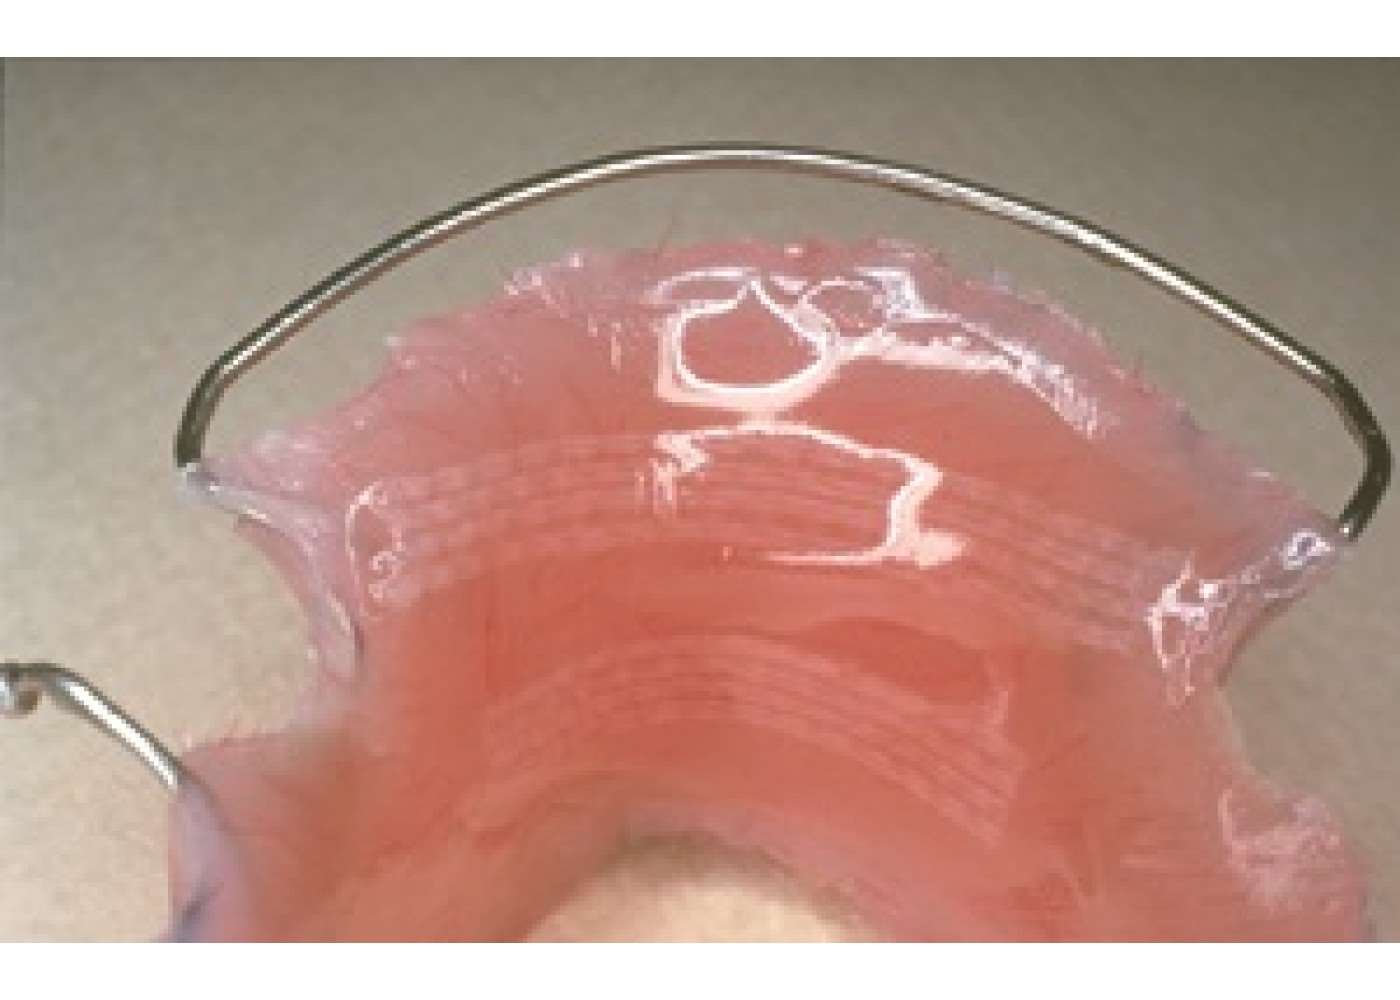

Η ειδική πλέξη σε συνδυασμό με το υλικό κατασκευής – ίνες που χρησιμοποιούνται για την κατασκευή αλεξίσφαιρων γιλέκων και προστατευτικής πανοπλίας για το στρατό – κάνει το Ribbond εξαιρετικά ανθεκτικό στη θραύση και είναι κατάλληλο για πολλές οδοντιατρικές εργασίες όπως: ναρθηκοποίηση, ενδορριζικούς άξονες, γέφυρες σε μία επίσκεψη, προσωρινές γέφυρες, αποκαταστάσεις ρητίνης σε μεγάλες κοιλότητες, διατήρηση κλείσιμου διαστήματος και σταθεροποίηση σε περίπτωση τραύματος.